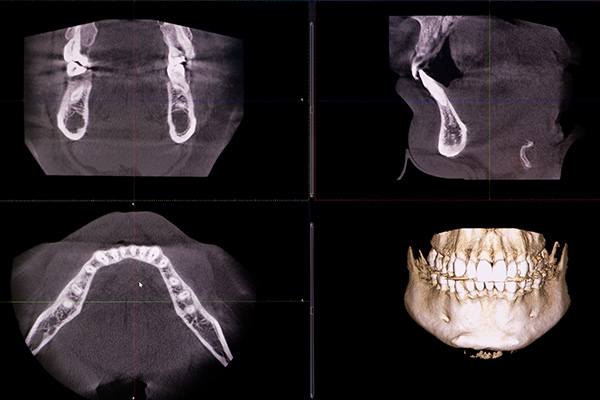

精密検査とシミュレーション

インプラント治療を安全に行うには、事前の徹底した準備が不可欠です。当院では、歯科用CTをはじめとした精密検査を行います。歯科用CTは、断増画像を画像処理することで、あごの骨や周囲の重要な組織(神経や血管など)を3次元で観察することを可能にします。

その精密検査で得たデータから、インプラントを埋入する位置、角度、深さを決定する詳細なシミュレーションを行い、より安全な確実な治療計画を立案します。